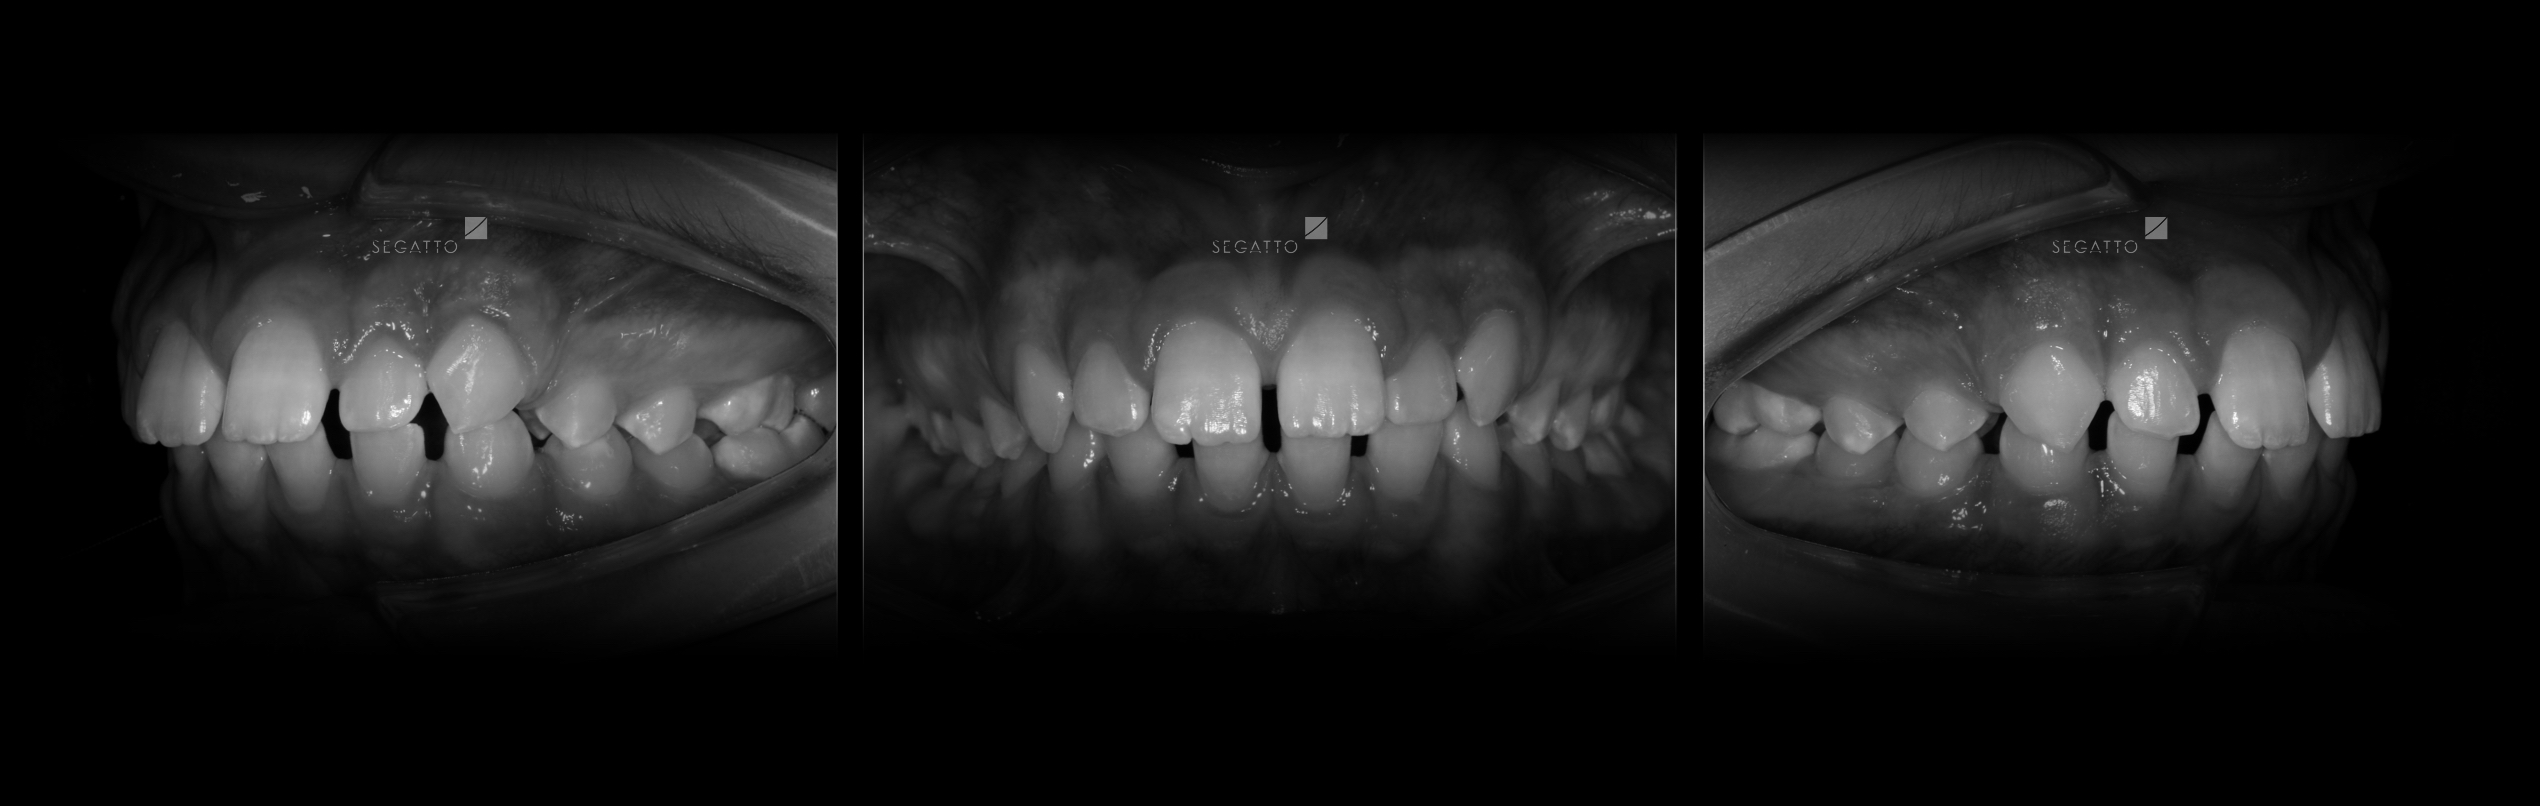

Orthodontics

Cases